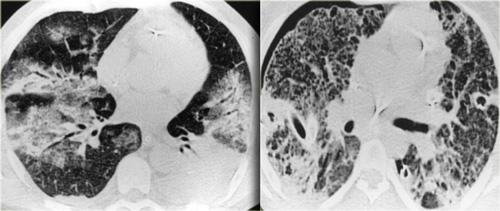

Bên trái là hai trường hợp NSIP.

Lưu ý sự kết hợp đa dạng giữa GGO và xơ hóa (giãn phế quản do co kéo), nhưng không có hình ảnh tổ ong.

Trong các hình ảnh bên trái, bạn có thể thấy lại phổ các dấu hiệu gặp trong NSIP.

Cả ba bệnh nhân đều mắc bệnh mô liên kết và tất cả các trường hợp đều được xác nhận bằng sinh thiết.

Trường hợp đầu tiên (trên bên trái) cho thấy GGO rất tinh tế.

Lưu ý sự khác biệt về tỷ trọng giữa không khí trong phế quản và nhu mô phổi xung quanh (dấu hiệu phế quản tối).

Trường hợp thứ hai (trên bên phải) là ví dụ rõ ràng hơn về GGO với các đậm độ dạng lưới mịn chồng lên do dày vách tiểu thùy.

Hình ảnh cuối cùng cũng cho thấy GGO với dạng lưới mịn.

Lưu ý sự vắng mặt của hình ảnh tổ ong trong cả ba trường hợp, loại trừ UIP là chẩn đoán.